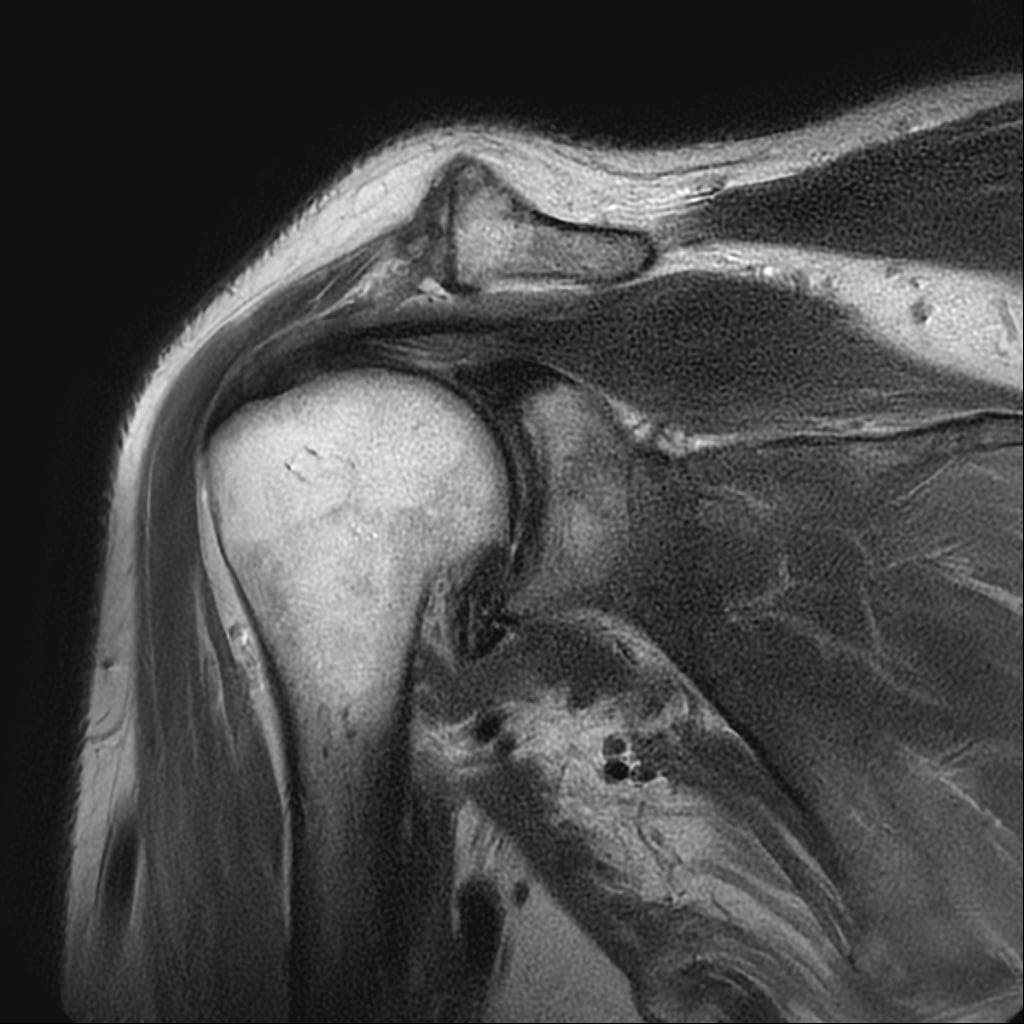

어깨 mri 상태인데 어디가 안 좋은가요?

해당사진으로 많은걸확인할수는없지만 회전근개손상을 의심해볼수있는데요 지속적으로 불편감이있다면 병원에서 검사와치료를받아보시길 바랍니다 감사합니다~

제가 직접 mri를 판독할 수는 없지만 일반적으로 어깨 mri에서 이상 소견이 자주 지적되는 부위는 회전근개 힘줄에 염증, 부분 파열, 손상이 흔합니다 또 견봉 아래 공간으로 충돌증후군이나 염증으로 공간이 좁아질 수 있습니다. 관절순은 탈구 벼력이 있으면 손상 가능성이 있어요 정확한 위치와 정도는 영상의학과 판독결과와 주치의 설명을 참고해야 합니다!

현재로썬 사진만으론 판단을 하긴 어렵지만 회전근개의 손상이 의심 갑니다.

회전근개 주변의 염증이나 손상이 발생하신 것으로 유추해볼 수 있겠습니다.

회전근개 손상은 어깨 관절 주변의 통증과 움직임 제한이 발생할 수 있으며,

완전 파열이 아닌 경우에는 보존적 치료를 우선 적용할 수 있습니다.